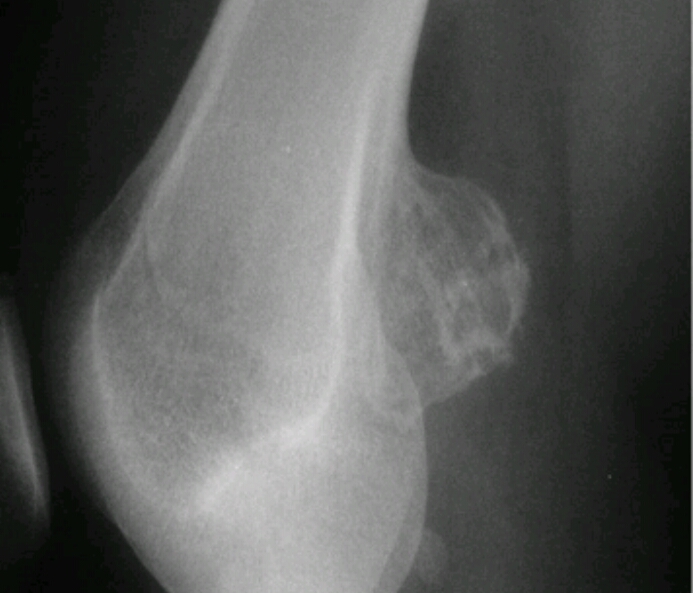

Sunburst periosteal reaction, dense sclerotic lesion at the proximal aspect of the humerus in the metaphyseal region, Codman triangle

Osteosarcoma